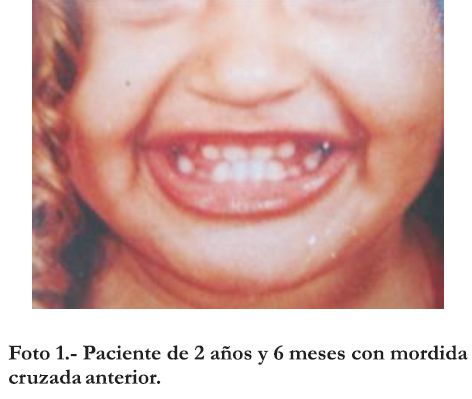

En una consulta de control, a los dos años y seis meses de edad, se constata el mantenimiento de la mordida cruzada anterior y atresia maxilar significativa. (Foto 1).